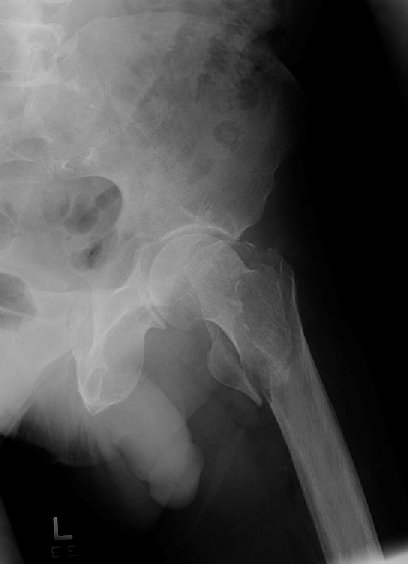

Return to Intertrochanteric Fracture